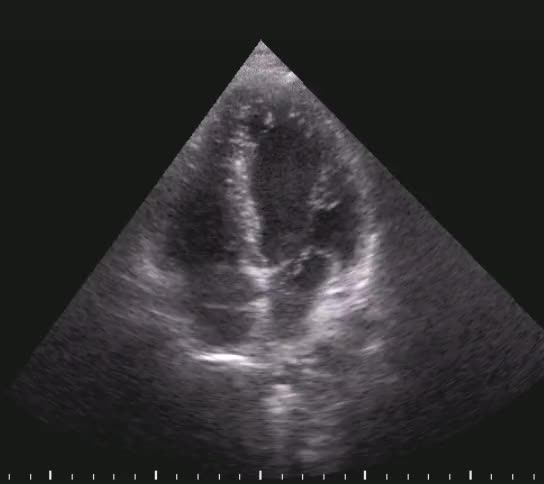

Titolo:

Trombosi della vena cava inferiore in embolia polmonare

Autore:

Chiara Bencini